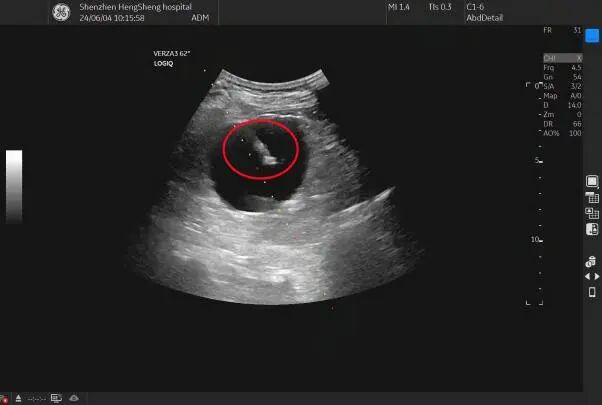

肾囊肿 - 超声医学讨论版 -丁香园论坛

5cm囊性液暗区,边界尚清,暗区清晰,如下图: 囊肿是超声医师最有信心的